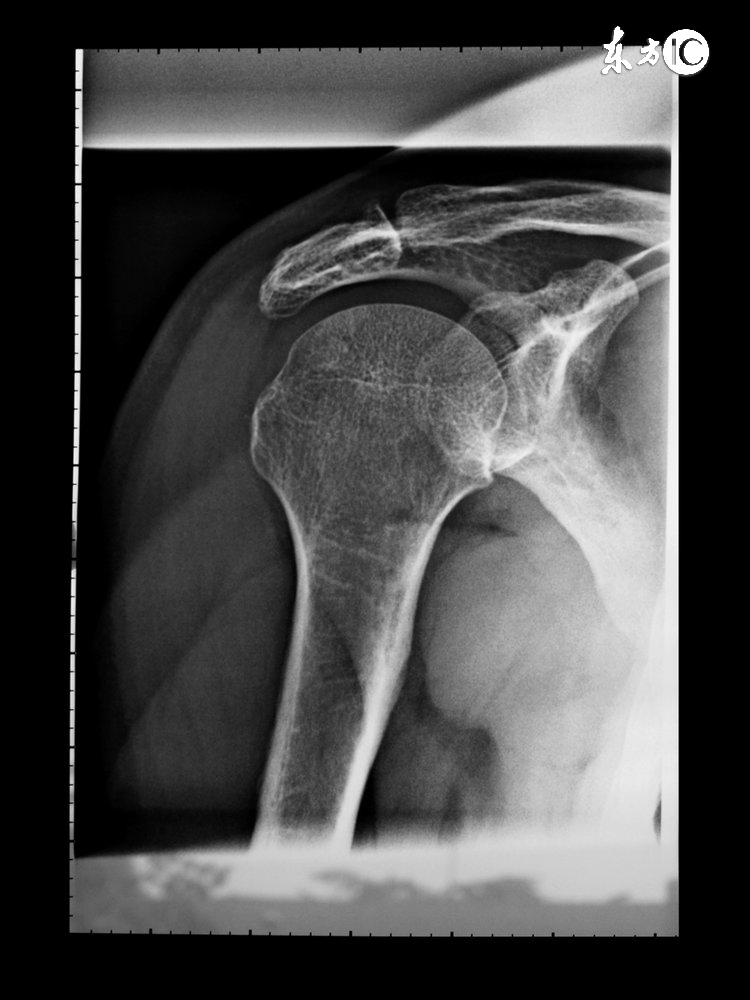

我有一个患者,六月中旬经人介绍找到了我。当时她右腿膝盖疼痛,尤其在上下楼的时候,要单腿错步才敢一节节的下楼梯,走平路时时间稍微长点(200米左右)就感觉到膝盖发软,无力支撑,需要休息一会儿才能继续行气。到医院拍片,影像显示在膝关节外侧下方有一游离体,故诊断上述症状是游离所致,啊、属于骨质增生,建议让手术取出此物,消除不适症状。

我用拇指按压她膝盖周边部位,发生右膝外侧上面部分有一明显压痛点,其他部位没有发现具体压痛点,但该压痛点与影视提示的游离体位置并不相同。我给她开了一个药酒方,灵仙50克,乳香没药各15克,川草乌各3克,麝香1克,回去后用白酒浸泡7日,7日后外涂病灶部位,也就是压痛点的地方,以缓解该部位的疼痛症状。同时嘱咐她让膝盖处于一种舒服的位置,不要过于劳损,平时注意保暖,不要受寒。